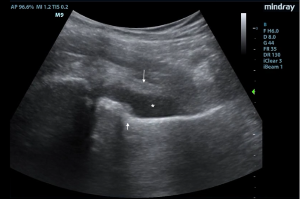

Initial ED course involved IV hydration, analgesia, and labs demonstrating ongoing leukocytosis with left shift, normal coagulation studies, and normal liver and renal function. Urine was sent for N. Gonorrhoeae and C. Trachomatis nucleic acid amplification tests. POCUS examination of bilateral hips revealed a 10 mm fluid collection anterior to the left femoral neck consistent with a hip effusion. Orthopedic surgery was consulted and requested an arthrocentesis, a procedure typically performed by an IR team at this institution, requiring time for transport, team organization, and room set-up. The EM team therefore elected to perform a POCUS-guided arthrocentesis.

With a linear array transducer positioned transversely over the inguinal region, the location of the femoral neurovascular bundle was marked using a surgical pen. The transducer was then rotated into a sagittal oblique position to visualize the hip effusion, and depth was measured to determine appropriate needle length. A low-frequency curvilinear probe was also briefly used to optimize visualization and to compare bilateral hips (Figures 1 and 2).

Under POCUS guidance, a 22-gauge 3.5-inch spinal needle was inserted distal to the long axis of the linear transducer and lateral to the femoral vessels. The needle was advanced in-plane to enter the anterior synovial recess and 10 ml of blood-tinged, purulent fluid was aspirated. There were no procedural complications and the patient had immediate resolution of pain with improved range of motion.